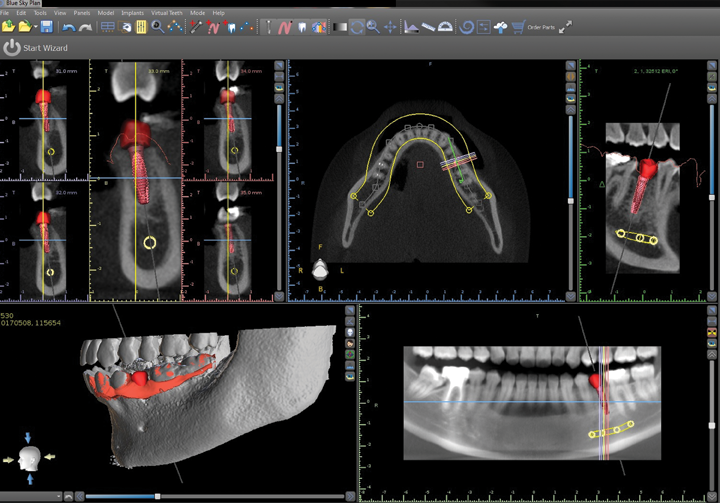

To start the process, we took an i-CAT CBCT at 16cm x 11cm as a 0.25 voxel size (Fig. 2). I chose a full field of view size because Yari had some dental issues on the lower right-hand side to check as well, so I needed to have additional information on that area.

Then, I captured an STL scan (Fig. 6) using PlanScan (E4D), an open source scanner that produces a vector file composed of thousands of tiny triangles that map out the 3D shape of the scanned area. Because i-CAT is also an open source, I am able to use both of these scans together in many third-party planning software programs. For this case, I used BlueSky Plan® to virtually and precisely place the implant (Figs. 7 and 8). I decided on the use of an OCO Biomedical 4 mm x 12 mm TSI implant with the guided implant kit.

Fig. 7 Fig. 8